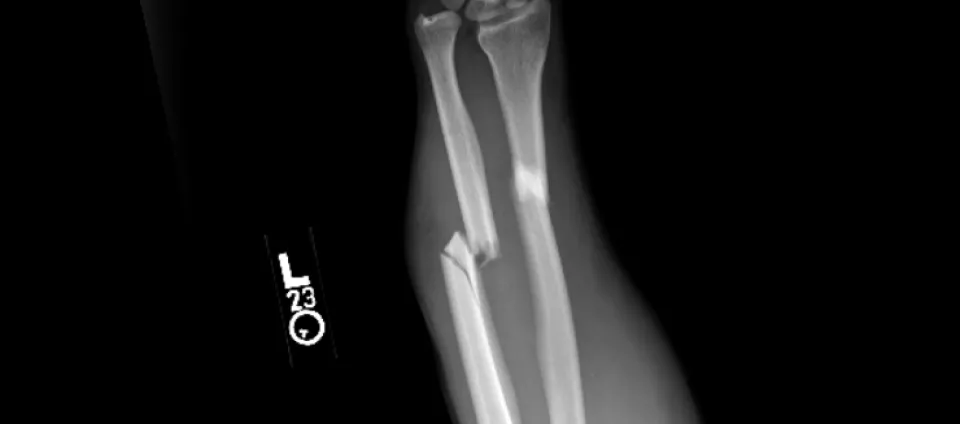

Bone injuries, known as fractures, are one of the most common reasons most people will visit an orthopedic surgeon. It is estimated that by 2025, in the US alone, 3 million fractures will occur every year. Some of this is driven by our aging population, but many of these occur in healthy young adults. In healthy individuals, fractures are usually related to higher energy trauma such as falls, sports injuries, and vehicle accidents.

At Pacific Crest Orthopedics, we customize a treatment plan to meet your individual needs. The fractures listed above are some of the most commonly seen, however, we treat all bone injuries. We put together a treatment plan depending on your type of fracture. Treatment can involve splinting, casting, or in some cases, surgical fixation. See more on our surgery treatments.